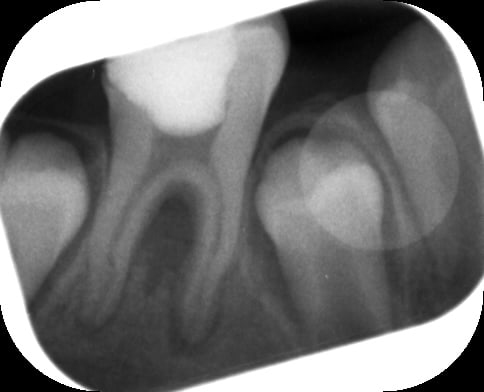

Voici des radios:

Post op2 hvhcb9 - Eugenol

En effet Belette, celle-ci c'est la radio post op du jour de l'endo. Ce jour là je me suis dit la même chose. La deuxième radio post op a été prise à J+3 et en distalant l'angle d'incidence du cône radio. Donc ce qu'on voit sur la deuxième radio ne correspond pas à une incidene orthogonale.